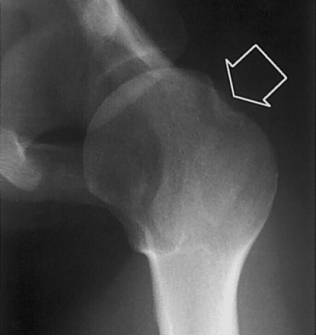

Hill-Sachs骨折

Hill-Sachs骨折指肱骨头压缩性骨折,当肩关节前脱位时,关节盂前缘撞击导致肱骨头后外侧压缩骨折。